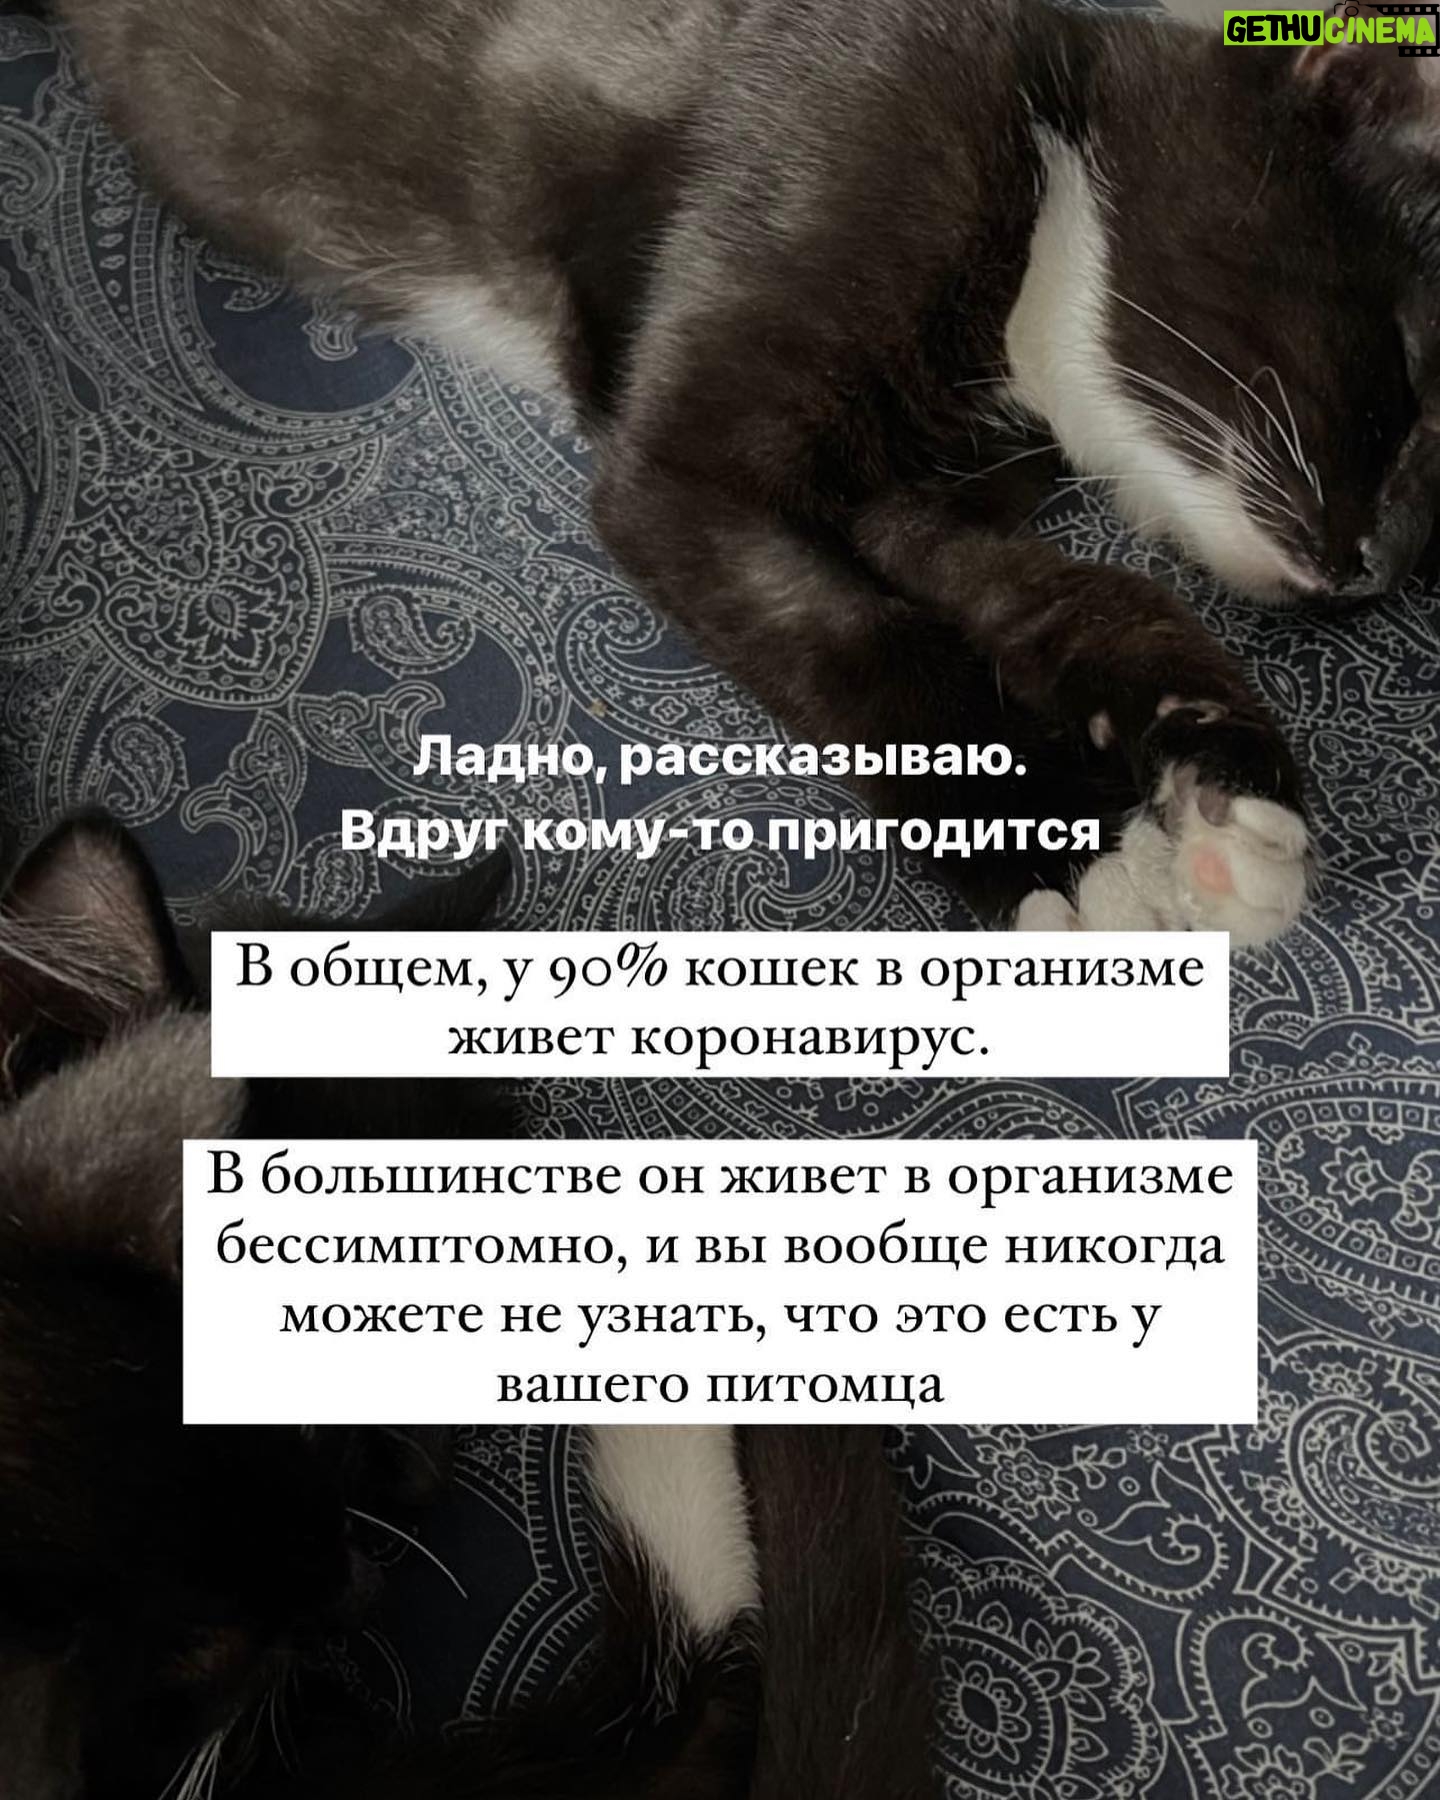

Caption : Про наших «блох», их болезнь и про классы от нас с @baturo_ Друзья, мы в конце января с Андреем взяли 3х котят из приюта. Прелестные, ласковые создания. К сожалению, двое из них заболели FIP (об этом рассказывала неделю назад, можно прочесть в карусели или в актуальном) Мы с Андреем уже очень сильно их любим, сдаваться не намерены. Четко и уверенно настроены на лучшее. Поэтому мы организовываем классы в Санкт-Петербурге 22 апреля‼️, все средства от которых пойдут на лечение наших блох, Нео и Абу. ⚫️22 апреля 15.00-17.00- Андрей Батуро (изоляция, виды) 17.00-19.00- Баина (партерная техника, основы безопасности в партере, грамотное распределение веса) ⚫️Стоимость: 1 класс-1500 руб 2 класса-2500 руб Место проведения: Jonathan, измайловский проспект, 2, зал 14 (вход со стороны измайловского проспекта) Код от домофона Внизу #1962 Наверху 2703# Проведите время с пользой для себя и помогите поправить здоровье двум маленьким котятам) Для записи пишите в директ) Мы очень будем рады видеть всех, а также просим максимально помочь с распространением этого поста, чтобы больше человек могли увидеть его)) P.S пользуясь случаем, хочу поблагодарить всех неравнодушных, кто просто захотел помочь монеткой🙏🏻🙏🏻 Это до слез ценно!Likes : 1330

Caption : Про наших «блох», их болезнь и про классы от нас с @baturo_ Друзья, мы в конце января с Андреем взяли 3х котят из приюта. Прелестные, ласковые создания. К сожалению, двое из них заболели FIP (об этом рассказывала неделю назад, можно прочесть в карусели или в актуальном) Мы с Андреем уже очень сильно их любим, сдаваться не намерены. Четко и уверенно настроены на лучшее. Поэтому мы организовываем классы в Санкт-Петербурге 22 апреля‼️, все средства от которых пойдут на лечение наших блох, Нео и Абу. ⚫️22 апреля 15.00-17.00- Андрей Батуро (изоляция, виды) 17.00-19.00- Баина (партерная техника, основы безопасности в партере, грамотное распределение веса) ⚫️Стоимость: 1 класс-1500 руб 2 класса-2500 руб Место проведения: Jonathan, измайловский проспект, 2, зал 14 (вход со стороны измайловского проспекта) Код от домофона Внизу #1962 Наверху 2703# Проведите время с пользой для себя и помогите поправить здоровье двум маленьким котятам) Для записи пишите в директ) Мы очень будем рады видеть всех, а также просим максимально помочь с распространением этого поста, чтобы больше человек могли увидеть его)) P.S пользуясь случаем, хочу поблагодарить всех неравнодушных, кто просто захотел помочь монеткой🙏🏻🙏🏻 Это до слез ценно!Likes : 1330

Caption : Про наших «блох», их болезнь и про классы от нас с @baturo_ Друзья, мы в конце января с Андреем взяли 3х котят из приюта. Прелестные, ласковые создания. К сожалению, двое из них заболели FIP (об этом рассказывала неделю назад, можно прочесть в карусели или в актуальном) Мы с Андреем уже очень сильно их любим, сдаваться не намерены. Четко и уверенно настроены на лучшее. Поэтому мы организовываем классы в Санкт-Петербурге 22 апреля‼️, все средства от которых пойдут на лечение наших блох, Нео и Абу. ⚫️22 апреля 15.00-17.00- Андрей Батуро (изоляция, виды) 17.00-19.00- Баина (партерная техника, основы безопасности в партере, грамотное распределение веса) ⚫️Стоимость: 1 класс-1500 руб 2 класса-2500 руб Место проведения: Jonathan, измайловский проспект, 2, зал 14 (вход со стороны измайловского проспекта) Код от домофона Внизу #1962 Наверху 2703# Проведите время с пользой для себя и помогите поправить здоровье двум маленьким котятам) Для записи пишите в директ) Мы очень будем рады видеть всех, а также просим максимально помочь с распространением этого поста, чтобы больше человек могли увидеть его)) P.S пользуясь случаем, хочу поблагодарить всех неравнодушных, кто просто захотел помочь монеткой🙏🏻🙏🏻 Это до слез ценно!Likes : 1330

Caption : Про наших «блох», их болезнь и про классы от нас с @baturo_ Друзья, мы в конце января с Андреем взяли 3х котят из приюта. Прелестные, ласковые создания. К сожалению, двое из них заболели FIP (об этом рассказывала неделю назад, можно прочесть в карусели или в актуальном) Мы с Андреем уже очень сильно их любим, сдаваться не намерены. Четко и уверенно настроены на лучшее. Поэтому мы организовываем классы в Санкт-Петербурге 22 апреля‼️, все средства от которых пойдут на лечение наших блох, Нео и Абу. ⚫️22 апреля 15.00-17.00- Андрей Батуро (изоляция, виды) 17.00-19.00- Баина (партерная техника, основы безопасности в партере, грамотное распределение веса) ⚫️Стоимость: 1 класс-1500 руб 2 класса-2500 руб Место проведения: Jonathan, измайловский проспект, 2, зал 14 (вход со стороны измайловского проспекта) Код от домофона Внизу #1962 Наверху 2703# Проведите время с пользой для себя и помогите поправить здоровье двум маленьким котятам) Для записи пишите в директ) Мы очень будем рады видеть всех, а также просим максимально помочь с распространением этого поста, чтобы больше человек могли увидеть его)) P.S пользуясь случаем, хочу поблагодарить всех неравнодушных, кто просто захотел помочь монеткой🙏🏻🙏🏻 Это до слез ценно!Likes : 1330

Caption : Про наших «блох», их болезнь и про классы от нас с @baturo_ Друзья, мы в конце января с Андреем взяли 3х котят из приюта. Прелестные, ласковые создания. К сожалению, двое из них заболели FIP (об этом рассказывала неделю назад, можно прочесть в карусели или в актуальном) Мы с Андреем уже очень сильно их любим, сдаваться не намерены. Четко и уверенно настроены на лучшее. Поэтому мы организовываем классы в Санкт-Петербурге 22 апреля‼️, все средства от которых пойдут на лечение наших блох, Нео и Абу. ⚫️22 апреля 15.00-17.00- Андрей Батуро (изоляция, виды) 17.00-19.00- Баина (партерная техника, основы безопасности в партере, грамотное распределение веса) ⚫️Стоимость: 1 класс-1500 руб 2 класса-2500 руб Место проведения: Jonathan, измайловский проспект, 2, зал 14 (вход со стороны измайловского проспекта) Код от домофона Внизу #1962 Наверху 2703# Проведите время с пользой для себя и помогите поправить здоровье двум маленьким котятам) Для записи пишите в директ) Мы очень будем рады видеть всех, а также просим максимально помочь с распространением этого поста, чтобы больше человек могли увидеть его)) P.S пользуясь случаем, хочу поблагодарить всех неравнодушных, кто просто захотел помочь монеткой🙏🏻🙏🏻 Это до слез ценно!Likes : 1330

Caption : Про наших «блох», их болезнь и про классы от нас с @baturo_ Друзья, мы в конце января с Андреем взяли 3х котят из приюта. Прелестные, ласковые создания. К сожалению, двое из них заболели FIP (об этом рассказывала неделю назад, можно прочесть в карусели или в актуальном) Мы с Андреем уже очень сильно их любим, сдаваться не намерены. Четко и уверенно настроены на лучшее. Поэтому мы организовываем классы в Санкт-Петербурге 22 апреля‼️, все средства от которых пойдут на лечение наших блох, Нео и Абу. ⚫️22 апреля 15.00-17.00- Андрей Батуро (изоляция, виды) 17.00-19.00- Баина (партерная техника, основы безопасности в партере, грамотное распределение веса) ⚫️Стоимость: 1 класс-1500 руб 2 класса-2500 руб Место проведения: Jonathan, измайловский проспект, 2, зал 14 (вход со стороны измайловского проспекта) Код от домофона Внизу #1962 Наверху 2703# Проведите время с пользой для себя и помогите поправить здоровье двум маленьким котятам) Для записи пишите в директ) Мы очень будем рады видеть всех, а также просим максимально помочь с распространением этого поста, чтобы больше человек могли увидеть его)) P.S пользуясь случаем, хочу поблагодарить всех неравнодушных, кто просто захотел помочь монеткой🙏🏻🙏🏻 Это до слез ценно!Likes : 1330

Caption : Про наших «блох», их болезнь и про классы от нас с @baturo_ Друзья, мы в конце января с Андреем взяли 3х котят из приюта. Прелестные, ласковые создания. К сожалению, двое из них заболели FIP (об этом рассказывала неделю назад, можно прочесть в карусели или в актуальном) Мы с Андреем уже очень сильно их любим, сдаваться не намерены. Четко и уверенно настроены на лучшее. Поэтому мы организовываем классы в Санкт-Петербурге 22 апреля‼️, все средства от которых пойдут на лечение наших блох, Нео и Абу. ⚫️22 апреля 15.00-17.00- Андрей Батуро (изоляция, виды) 17.00-19.00- Баина (партерная техника, основы безопасности в партере, грамотное распределение веса) ⚫️Стоимость: 1 класс-1500 руб 2 класса-2500 руб Место проведения: Jonathan, измайловский проспект, 2, зал 14 (вход со стороны измайловского проспекта) Код от домофона Внизу #1962 Наверху 2703# Проведите время с пользой для себя и помогите поправить здоровье двум маленьким котятам) Для записи пишите в директ) Мы очень будем рады видеть всех, а также просим максимально помочь с распространением этого поста, чтобы больше человек могли увидеть его)) P.S пользуясь случаем, хочу поблагодарить всех неравнодушных, кто просто захотел помочь монеткой🙏🏻🙏🏻 Это до слез ценно!Likes : 1330

Caption : Про наших «блох», их болезнь и про классы от нас с @baturo_ Друзья, мы в конце января с Андреем взяли 3х котят из приюта. Прелестные, ласковые создания. К сожалению, двое из них заболели FIP (об этом рассказывала неделю назад, можно прочесть в карусели или в актуальном) Мы с Андреем уже очень сильно их любим, сдаваться не намерены. Четко и уверенно настроены на лучшее. Поэтому мы организовываем классы в Санкт-Петербурге 22 апреля‼️, все средства от которых пойдут на лечение наших блох, Нео и Абу. ⚫️22 апреля 15.00-17.00- Андрей Батуро (изоляция, виды) 17.00-19.00- Баина (партерная техника, основы безопасности в партере, грамотное распределение веса) ⚫️Стоимость: 1 класс-1500 руб 2 класса-2500 руб Место проведения: Jonathan, измайловский проспект, 2, зал 14 (вход со стороны измайловского проспекта) Код от домофона Внизу #1962 Наверху 2703# Проведите время с пользой для себя и помогите поправить здоровье двум маленьким котятам) Для записи пишите в директ) Мы очень будем рады видеть всех, а также просим максимально помочь с распространением этого поста, чтобы больше человек могли увидеть его)) P.S пользуясь случаем, хочу поблагодарить всех неравнодушных, кто просто захотел помочь монеткой🙏🏻🙏🏻 Это до слез ценно!Likes : 1330

Caption : Про наших «блох», их болезнь и про классы от нас с @baturo_ Друзья, мы в конце января с Андреем взяли 3х котят из приюта. Прелестные, ласковые создания. К сожалению, двое из них заболели FIP (об этом рассказывала неделю назад, можно прочесть в карусели или в актуальном) Мы с Андреем уже очень сильно их любим, сдаваться не намерены. Четко и уверенно настроены на лучшее. Поэтому мы организовываем классы в Санкт-Петербурге 22 апреля‼️, все средства от которых пойдут на лечение наших блох, Нео и Абу. ⚫️22 апреля 15.00-17.00- Андрей Батуро (изоляция, виды) 17.00-19.00- Баина (партерная техника, основы безопасности в партере, грамотное распределение веса) ⚫️Стоимость: 1 класс-1500 руб 2 класса-2500 руб Место проведения: Jonathan, измайловский проспект, 2, зал 14 (вход со стороны измайловского проспекта) Код от домофона Внизу #1962 Наверху 2703# Проведите время с пользой для себя и помогите поправить здоровье двум маленьким котятам) Для записи пишите в директ) Мы очень будем рады видеть всех, а также просим максимально помочь с распространением этого поста, чтобы больше человек могли увидеть его)) P.S пользуясь случаем, хочу поблагодарить всех неравнодушных, кто просто захотел помочь монеткой🙏🏻🙏🏻 Это до слез ценно!Likes : 1330

Caption : Про наших «блох», их болезнь и про классы от нас с @baturo_ Друзья, мы в конце января с Андреем взяли 3х котят из приюта. Прелестные, ласковые создания. К сожалению, двое из них заболели FIP (об этом рассказывала неделю назад, можно прочесть в карусели или в актуальном) Мы с Андреем уже очень сильно их любим, сдаваться не намерены. Четко и уверенно настроены на лучшее. Поэтому мы организовываем классы в Санкт-Петербурге 22 апреля‼️, все средства от которых пойдут на лечение наших блох, Нео и Абу. ⚫️22 апреля 15.00-17.00- Андрей Батуро (изоляция, виды) 17.00-19.00- Баина (партерная техника, основы безопасности в партере, грамотное распределение веса) ⚫️Стоимость: 1 класс-1500 руб 2 класса-2500 руб Место проведения: Jonathan, измайловский проспект, 2, зал 14 (вход со стороны измайловского проспекта) Код от домофона Внизу #1962 Наверху 2703# Проведите время с пользой для себя и помогите поправить здоровье двум маленьким котятам) Для записи пишите в директ) Мы очень будем рады видеть всех, а также просим максимально помочь с распространением этого поста, чтобы больше человек могли увидеть его)) P.S пользуясь случаем, хочу поблагодарить всех неравнодушных, кто просто захотел помочь монеткой🙏🏻🙏🏻 Это до слез ценно!Likes : 1330